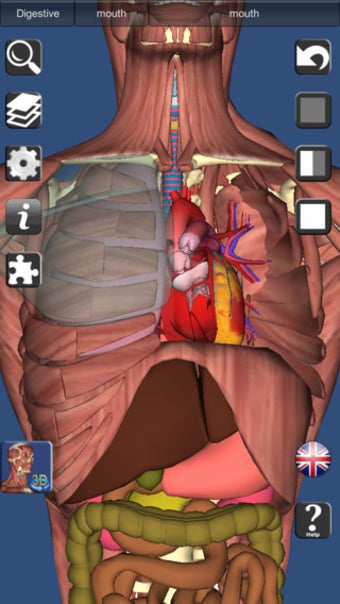

يشبه 3D Anatomy Lite سلسلة Essential Anatomy من التطبيقات من حيث أنه يوفر ميزة ممتازة أداة ثلاثية الأبعاد للمعلمين والطلاب وعشاق الطب العام من أجل استكشاف جسم الإنسان strong>.

على الرغم من أنها لا تبدو رائعة مثل Essential Anatomy ، إلا أنها مفصلة مع القدرة على اعرض النص من أي زاوية strong> بالرغم من أنه يتعين عليك الترقية إلى الإصدار الكامل لمشاهدة كل شيء. p> هناك أيضًا اختبارات ثلاثية الأبعاد strong> لاختبار تكوين معرفتك 3D Anatomy Lite مصدر ممتاز للطلاب. p>